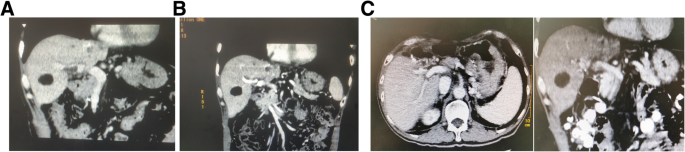

The patient had been followed every two months after surgery for 20 months, and no obvious tumor recurrence was observed. Moreover, the portal vein tumor thrombus was gradually reduced, and had disappeared after the sixth chemotherapy course (Fig. 4).

Representative computed tomography scan images after operation. a: A computed tomography scan images 2 months after the operation. Portal vein tumor thrombus reduced significantly. b: Computed tomography scan images 6 months after the operation. There were no portal vein filling defects, portal vein tumor thrombus was not overtly present in CT images. c: Computed tomography scan images 20 months after the operation. There was no tumor recurrence, portal vein tumor thrombus was not observable in the CT images

In this case, one month after the operation, portal vein infusion chemotherapy of FOLFOX regimen was performed every three weeks. The chemotherapy procedure went smoothly and the patient did not complain of any discomfort. Post-operative follow-up showed that the PVTT gradually reduced. Although the primary PVTT was clear, the left PVTT was present two months after the operation, while there was no portal vein filling defects after undergoing six chemotherapy courses, six months after the operation. These middle to long-term positive outcomes were considered to be attributable to the portal vein infusion chemotherapy. It proved that IORT and portal vein infusion chemotherapy is effective and safe, and played a comprehensive role in PVTT subsequent treatment.